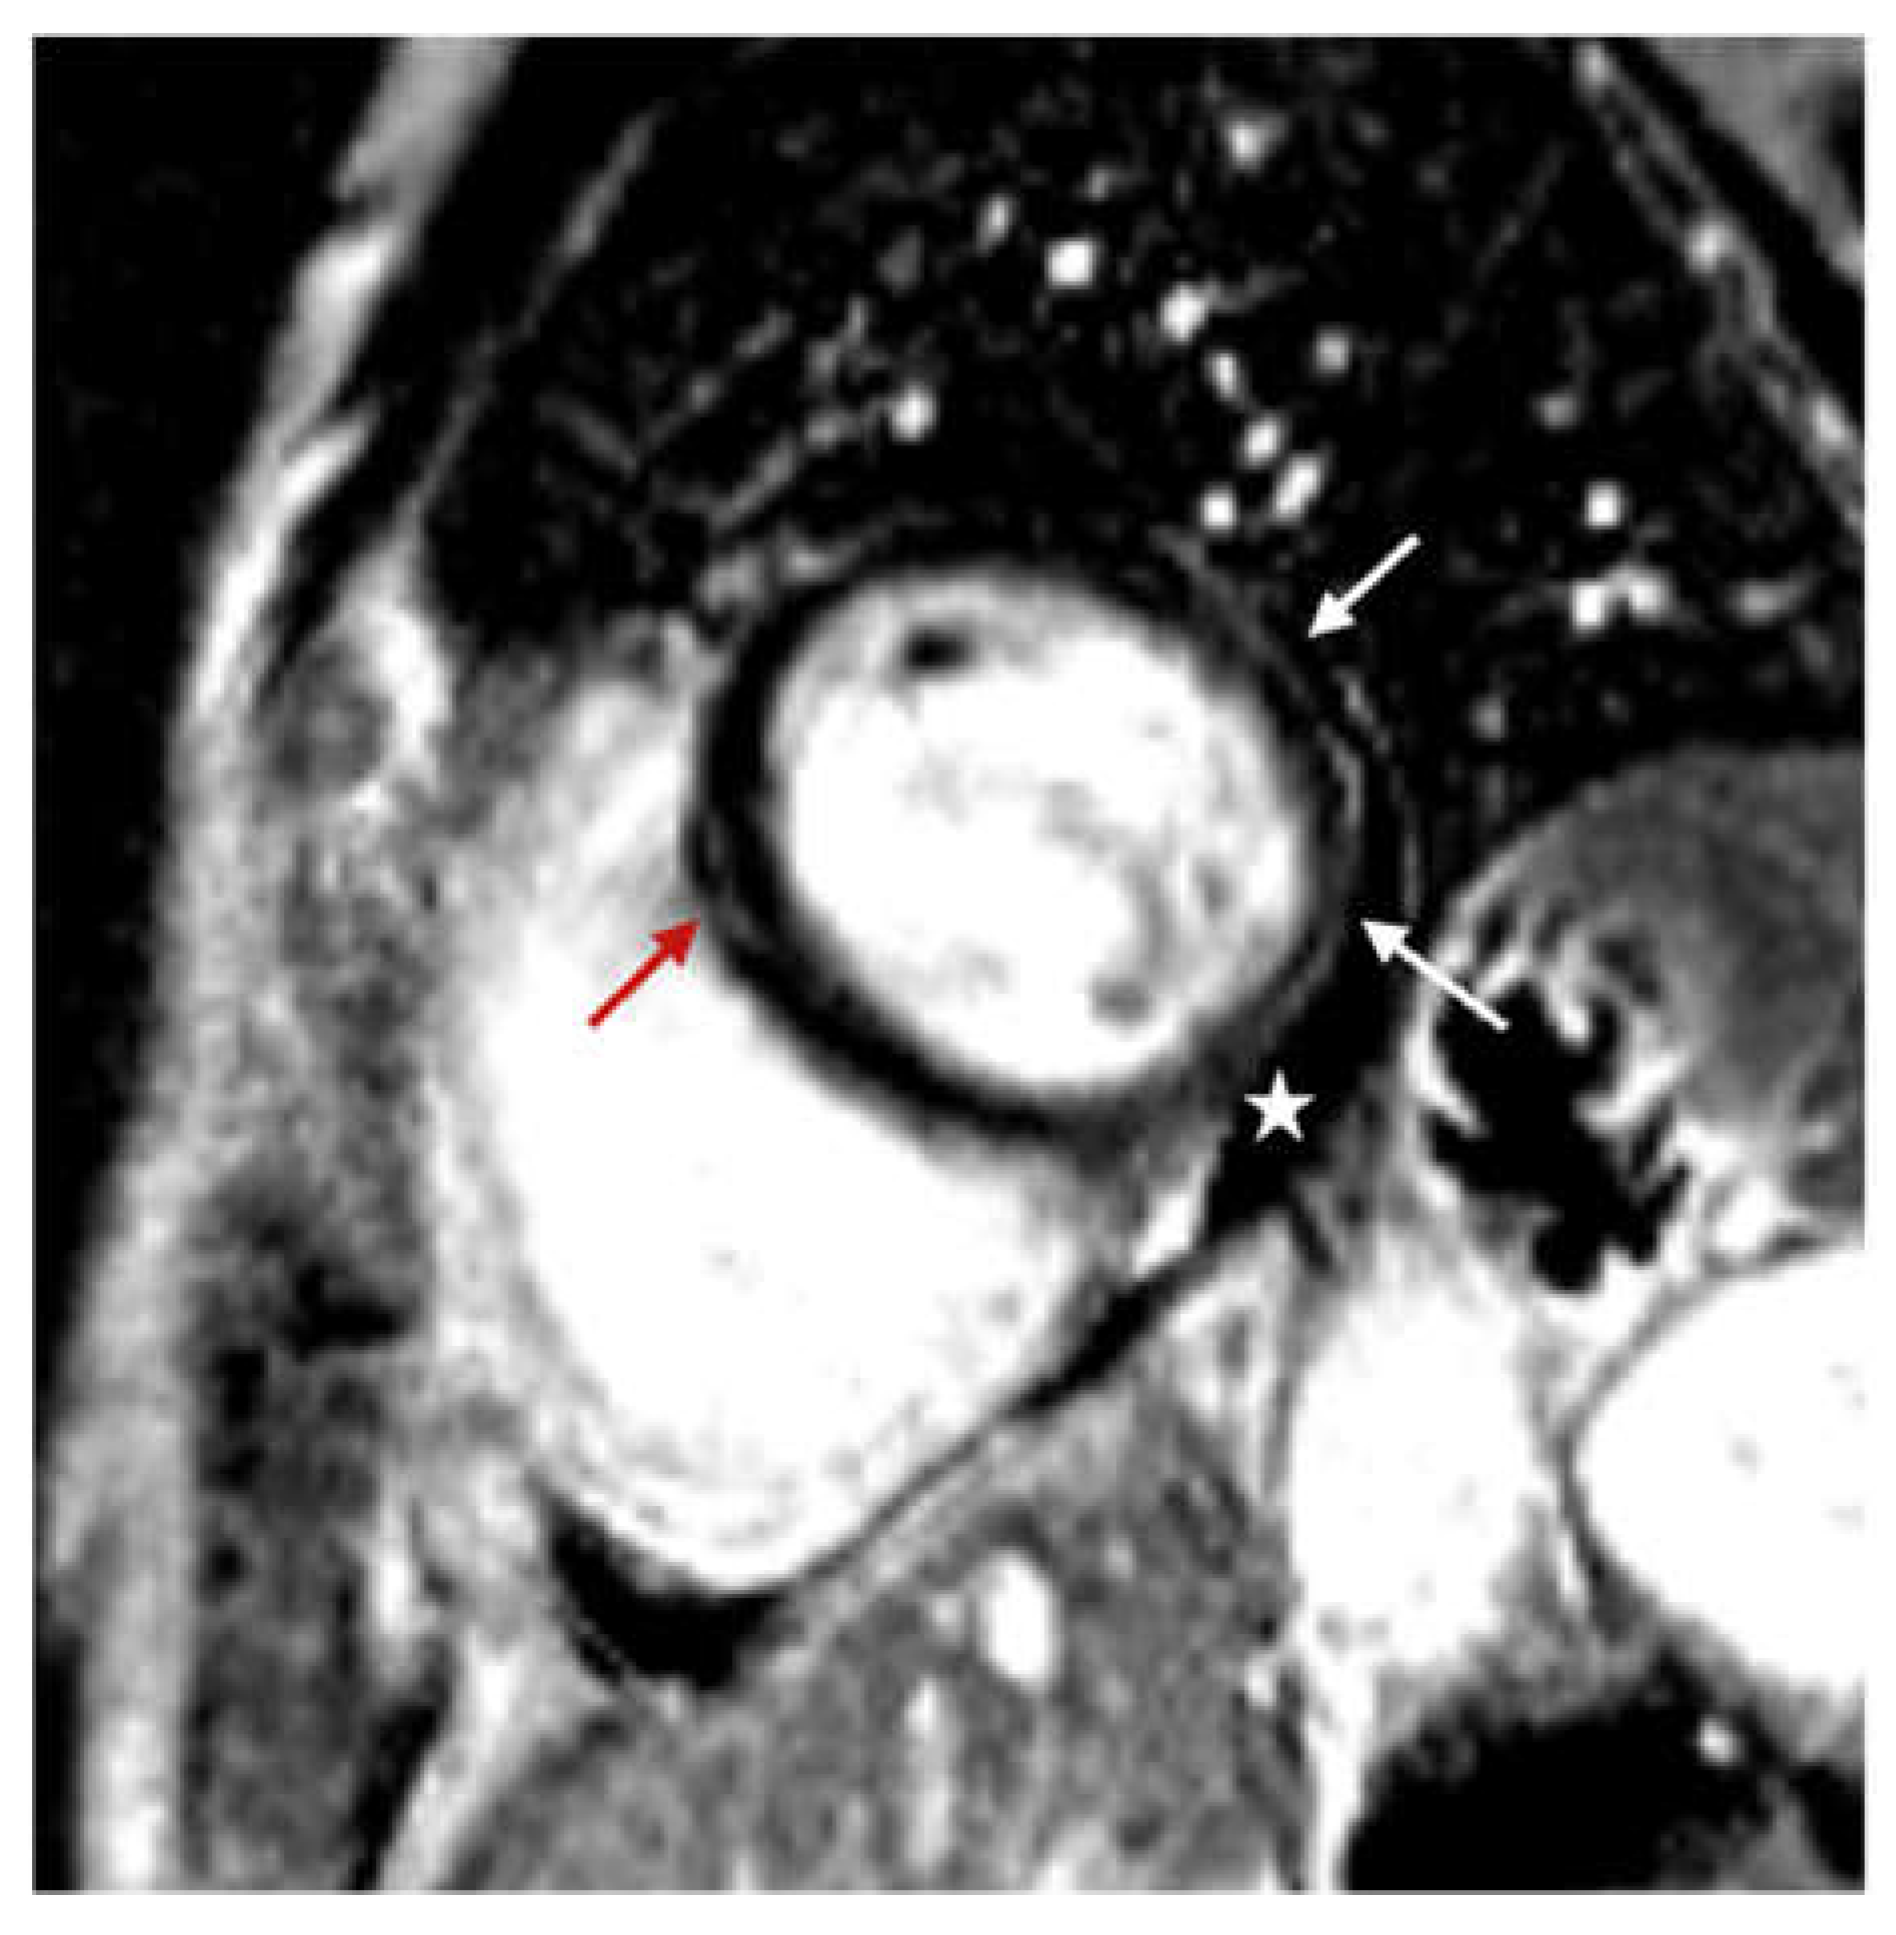

The findings of our research showed that the phenomenon of late pericardial enhancement was present in 40% of the included patients, while mild pericardial effusion (<10 mm) was present in more than half of the included patients (51.8%) (Figure 4). These results are similar to those obtained by Brito et al. in a study that investigated the spectrum of cardiac abnormalities in previously healthy student-athletes recovering from uncomplicated COVID-19 infection [43]. The existence of pericardial effusion during COVID-19 infection is explained by several pathophysiological mechanisms: (a) by binding to the ACE2 receptor, the virus directly invades cardiomyocytes leading to myocardial injury; (b) indirectly, by means of inflammatory cytokines (tumor necrosis factor-alpha (TNF-a), interleukin (IL)-1, and IL-6) the virus leads to pericarditis or myopericarditis; (c) result of direct involvement of the pericardium; (d) consequence of acute respiratory distress syndrome (ARDS) or hypoxia [44]. Saraç et al. investigated the clinical significance of pericardial effusion (prevalence, risk factors, prognosis, late clinical outcomes, and treatment) in patients discharged after recovery from COVID-19 [44]. Their study showed that in 75.9% of patients with an initial small pericardial effusion, after a follow-up of 25 months, there was a complete resolution of the effusion, but it also showed that there was a progression of the effusion in patients with more severe disease, which consequently led to an increase in the frequency of hospitalization for recurrent cardiac and non-cardiac reasons, complications, and mortality rates. Follow-up studies after COVID-19 indicate an increased risk of cardiovascular events, including pericardial disease. It has been shown that the presence of pericardial effusion in patients in the post-COVID-19 period is one of the main risk factors and a poor prognostic indicator regarding the occurrence of complications during the acute and chronic phase [44,45].

Figure 4.

Cine sequences, mid-ventricular short axis slice: mild (<10 mm) pericardial effusion (marked with arrows).

Our study compared quality of life during the post-COVID-19 period with CMR findings and showed that post-COVID-19 quality of life is worse in patients with CMR abnormalities (pericardial effusion and LGE) (Figure 5). Pericardial effusion was more often observed in patients who had more severe symptoms and lower quality of life during the post-COVID-19 period. Also, irregular heartbeat, cardiovascular symptoms that last longer than 12 weeks, as well as pericardial effusion, were independent predictors of lower quality of life during the post-COVID-19 period. It is important to note that we did not observe a significant correlation between the severity of acute COVID-19 infection and lower quality of life during the post-COVID-19 period (Table 6). Current data indicate that persistent cardiac symptoms in post-COVID-19 patients are mainly associated with the existence of active or healed myocarditis, which may be a consequence of a slower resolution of the inflammatory process or its transition to a chronic phase, which can potentially cause long-term damage to the myocardium [46,47].

Figure 5.

Phase-sensitive inversion recovery (PSIR), basal ventricular short axis slice: mid-wall distribution of late gadolinium enhancement (LGE) in basal anteroseptal segment (red arrow); subepicardial distribution of late gadolinium enhancement (LGE) in basal inferior and inferolateral segments (white arrow); pericardial effusion (star).